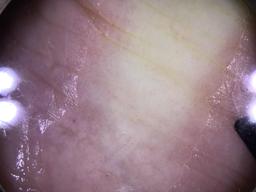

This dataset contains detailed skin tone annotations collected from a prospective, single-center observational study performed at Memorial Sloan Kettering Cancer Center from 2023-2024. The cohort consists of 64 adult patients who underwent full-body skin examinations by board-certified dermatologists. To ensure diverse representation across the spectrum of skin tones, patients were recruited to achieve a balanced distribution across all six Fitzpatrick Skin Types. This dataset was developed to evaluate the reliability of different skin tone labeling methods and to support fairness research in dermatologic AI.

The dataset comprises both patient-level and site-level metadata for skin tone classification using the Fitzpatrick Skin Type scale, Monk Skin Tone scale, Pantone SkinTone Guide, and colorimeter readings (SkinColorCatch, Delfin Technologies). A total of 4,879 dermoscopic images are included. Skin tone assessments were collected across both lesional and non-lesional (normal skin) sites, mapped to standardized anatomic locations. All skin lesions are assumed to be benign, as they were imaged immediately following dermatologic evaluation.